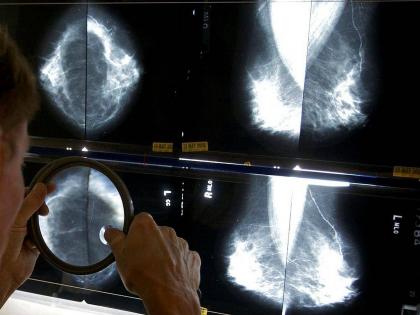

ब्रेस्ट कॅन्सरची माहिती रेडिओलॉजिस्ट लावू शकतील अथवा नसेल, पण आर्टिफिशिअल इंटेलिजन्स ब्रेस्ट कॅन्सरची माहिती त्याच्या सुरूवातीच्या लक्षणांवरूनच मिळवू शकतं. असं आमचं नाही तर गुगलचं मत आहे. कंपनीने दावा केला आहे की, कंपनीकडून एक असं एआय(आर्टिफिशिअल इंजेलिजन्स) मॉडल विकसित केलंय, ज्याने ब्रेस्ट कॅन्सर होण्याचे संकेत आधीच माहीत करून घेता येतील.

कंपनीकडून त्यांच्या एका ब्लॉगमध्ये लिहिले आहे की, टेस्टींगदरम्यान समोर आले की, ६ ह्यूमन रेडिओलॉजिस्टची तुलना एआयने फार सहजपणे आणि चांगल्या प्रकारे रूग्णातील ब्रेस्ट कॅन्सरच्या लक्षणांना ओळखण्यात यश मिळवलं. गुगल या विषयावर त्यांच्या युनायटेड किंगडम आणि युनायटेड स्टेटच्या क्लिनिकल रिसर्च पार्टनर्ससोबत मिळून गेल्या दोन वर्षांपासून अभ्यास करत आहे. कंपनीने याबाबत काही ठोस पुरावे असल्याचाही दावा केला आहे.

मीडिया रिपोर्ट्सनुसार, एआय मॉडलला ट्रेन्ड अॅन्ड ट्यून्ड केलं गेलं होतं. यादरम्यान यात कॅन्सरची माहिती मिळवण्यासाठी वापरलेल्या स्तनांचा एक्स-रे आणि मेमोग्राम डेटा फीड केला गेला होता. हा डेटा यूकेतील ब्रेस्ट कॅन्सरच्य ७६ रूग्णांचा आणि यूएसमधील १५ हजार रूग्णांना होता. कंपनीकडून असंही सांगण्यात आलं आहे की, डेटा रिकगनाजेशन दरम्यान एआयला टेस्ट करण्यासाठी ज्या फॉल्स डेटाची वापर केला गेला, एआयने फार हुशारीने त्यांना ओळखून वेगळं केलं.